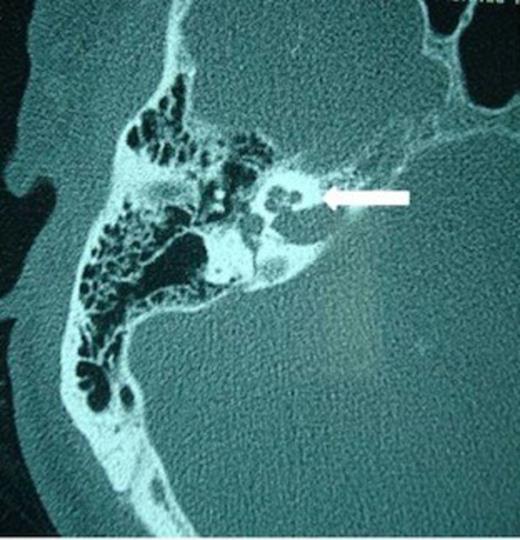

A 52 –year-old male with bilateral deafness and right facial nerve palsy presented to our clinic. The patient who was referred for consideration of cochlear implantation had a history of head injury 8 months before. An initial CT scan 2 months following his injury showed a transverse temporal bone fracture on the right side and a longitudinal one on the left side. Both cochleas appeared to be patent (Fig. 1, 2). The left ear was chosen for implantation as the injury was less severe on that side.

Right transverse fracture (black arrow) and left longitudinal fracture (white arrow)

When surgery was attempted, cochleostomy revealed complete obliteration of the scala tympani. Efforts to insert the electrode through the scala vestibuli were also unsuccessful. The procedure was abandoned and a subsequent high resolution CT scan showed complete ossification of the left cochlea and but a patent cochlea on the right (Fig. 3 and 4). Twenty days following the initial attempt, a right cochlear implantation was successfully performed. Following mapping, programming, and aural rehabilitation, the patient was able to understand speech and use the telephone.